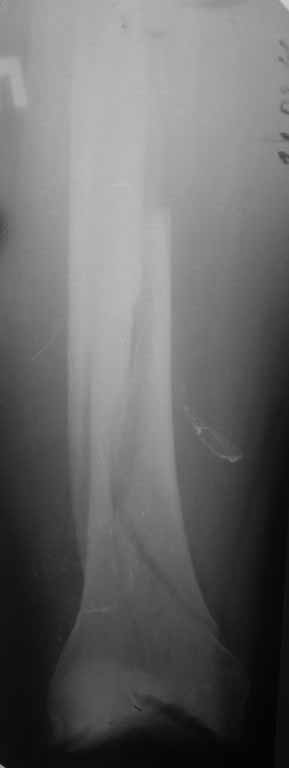

Представляю вам один из наших недавних случаев выполнения малоинвазивного остеосинтеза бедренной кости обычной пластиной 95 градусов. Длина восстановлена с помощью дистрактора (по сути это основная и б(о)льшая часть репозиции). Произведено два небольших доступа, проведена спица направитель. Рентген-контроль для подтверждения достаточной длины/оси (ЭОП использовался в другой операционной). Создание туннеля обратной стороной фиксатора. Поворот фиксатора, введение клинка по спице. Фиксация проксимального и дистального концов пластины.

[ Ответить ]